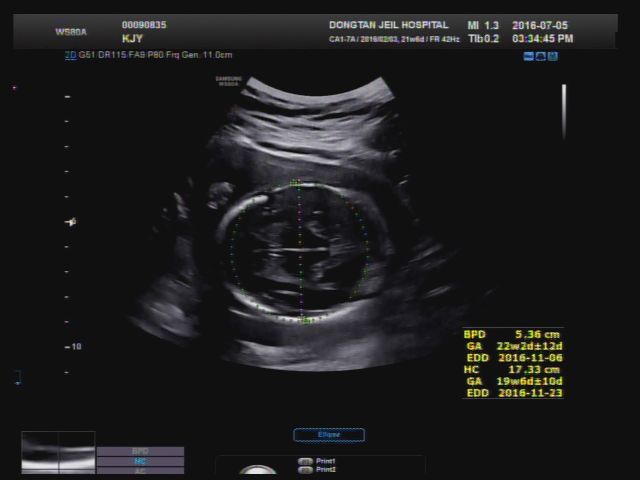

[21w6d] 2016년 7월 5일 2차 정밀초음파, 냉검사

2차 정밀 초음파 보러가는날! 장기 형성이 잘 되고 있는지 초음파로 꼼꼼하게 확인하는 날이다- 하.. 장마....